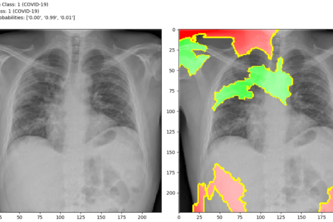

An AI solution on Detecting COVID-19 signs

Don't scram before you scan! Upload your scan on our application which, using a reliable deep learning network in the back-end diagnoses whether the patient is COVID positive or negative.

Screening system for detecting COVID-19 using chest x-rays and CT scans